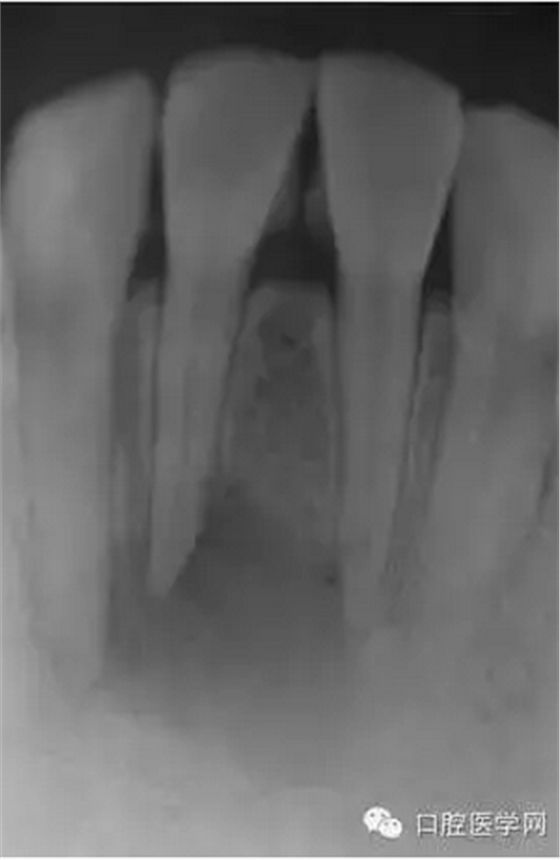

23歲女性患者,下頜右前牙的唇側(cè)有嚴(yán)重腫脹和疼痛。相應(yīng)部位有過外傷史,但記不起是什么時(shí)候了。放射線照片顯示以右下頜中切牙為中心,有波及右下側(cè)切牙及左下中切牙的大范圍的根尖周病變,臨床檢查時(shí),無齲壞,只發(fā)現(xiàn)右下中切牙略有變色,牙髓活力檢查(電子牙髓檢查及冷檢查)發(fā)現(xiàn),右下中切牙無反應(yīng),而鄰近齒表現(xiàn)為正常。判斷大范圍的根尖周病變的原因是受過外傷的右下中切牙的牙髓壞死,受周邊環(huán)境影響,發(fā)展為急性根尖周膿腫。

(圖 1) 初診的放射線照片